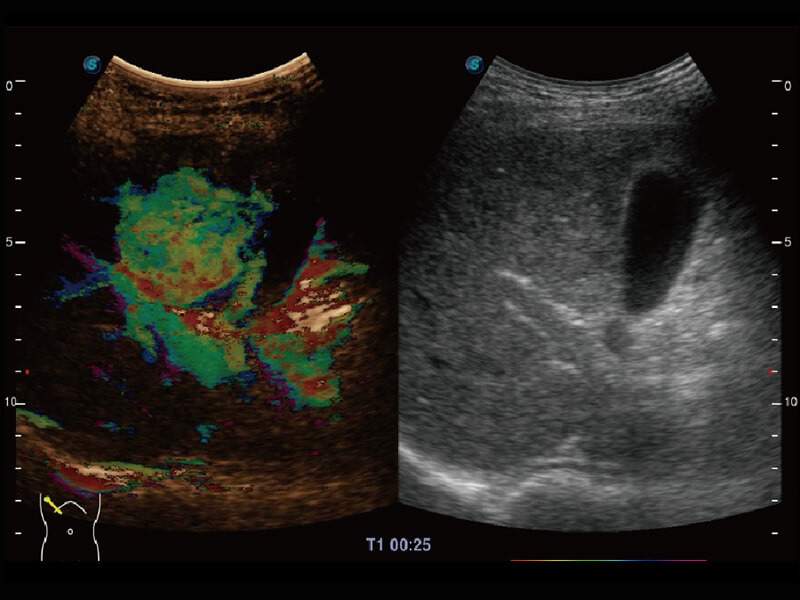

彩色多普勒超声诊断系统

S60探头工艺,从前端信号处理每一个环节采集无损声学数据,真实还原组织原貌,再现解剖细节。